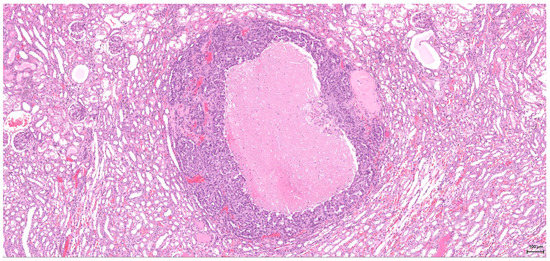

A sarcomatoid pattern is encountered in five cases (2–6) in various proportions, showing spindle cell morphology and exhibiting rhabdoid features in one case. The tumour invasion front is infiltrative; entrapped glomeruli and unaffected tubuli within the tumour mass are noted. The three cases with large sarcomatoid areas (4–6, one of which had associated rhabdoid features), have an aggressive biological behaviour; vascular and neural invasion (Figure 2) are seen. These tumours are no longer organ-confined; they manifest a marked locally invasive capacity with distant metastases (lung, liver).

Figure 2. H&E: Male (case 4): high-grade tumour with aggressive behaviour, infiltrating the perirenal fat (bottom right), nerves (arrow) and part of an autonomic ganglion (top left).